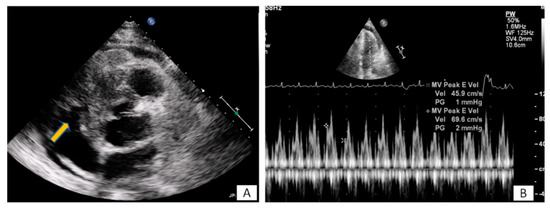

3.1. Transthoracic Echocardiography